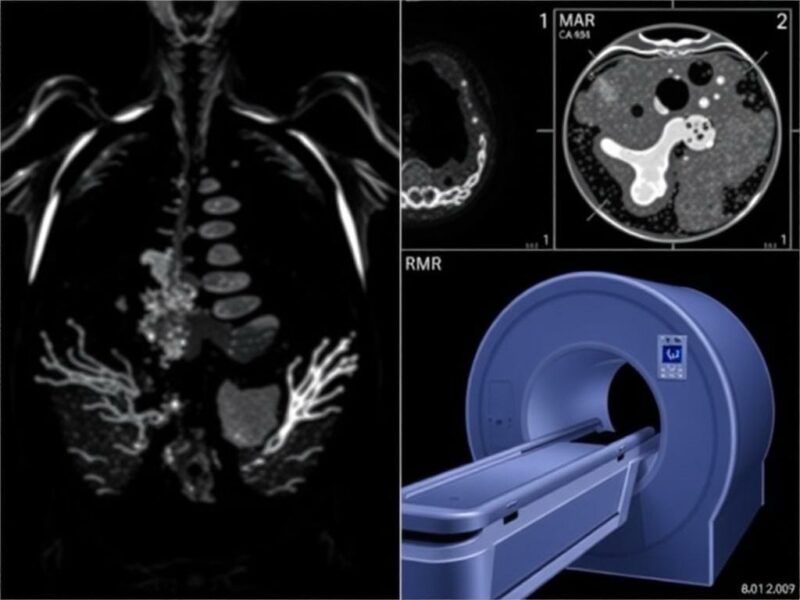

La resonancia magnética utiliza campos magnéticos fuertes y ondas de radio para generar imágenes detalladas de los tejidos corporales. A diferencia de la ecografía, la RM ofrece una visión muy detallada de las estructuras internas, especialmente de tejidos blandos como el cerebro, la médula espinal, el hígado, los músculos y las articulaciones. No emplea radiación ionizante, y eso la convierte en una alternativa potente cuando se desea evitar rayos X o TC, pero se necesita una resolución diagnóstica superior.

Una de las grandes ventajas de la RM es su capacidad para diferenciar tipos de tejidos y detectar cambios que podrían pasar desapercibidos en otros estudios. Con secuencias específicas, la RM puede evaluar edema, inflamación, tejido necrótico, hemorragias y comportamiento vascular sin la necesidad de irradiación. Además, existe la resonancia con contraste (gadolinio), que mejora la detección de determinados procesos sin las preocupaciones sobre radiación, aunque con sus propias consideraciones relativas al uso de contraste.

Otra fortaleza es la capacidad multiplanar y la reconstrucción tridimensional precisa de estructuras complejas. Esto hace que la RM sea la herramienta de referencia en neurología, ortopedia y ciertas áreas de oncología. Además, en muchos centros se desarrollan protocolos de RM abreviada para reducir tiempo y coste, manteniendo sensibilidad diagnóstica para problemas específicos.

La resonancia no está exenta de limitaciones prácticas. Es más costosa y menos accesible que la ecografía, y su duración de estudio puede resultar incómoda para pacientes claustrofóbicos o inestables. Algunos pacientes no pueden someterse a RM debido a implantes metálicos, marcapasos incompatibles o fragmentos metálicos en órganos vitales. Aunque la tecnología avanza y muchos dispositivos actuales son compatibles con RM, la precaución es necesaria.

Otro aspecto es la necesidad ocasional de sedación en niños o personas que no toleran permanecer quietas. Además, el tiempo de espera para una RM en centros con alta demanda puede ser largo, lo que dificulta su utilización como prueba de primera línea en situaciones agudas. En cuanto al gadolinio, aunque generalmente seguro, su uso requiere evaluación renal previa y existe discusión sobre su acumulación en tejidos tras exposiciones repetidas, lo cual debe considerarse con prudencia.